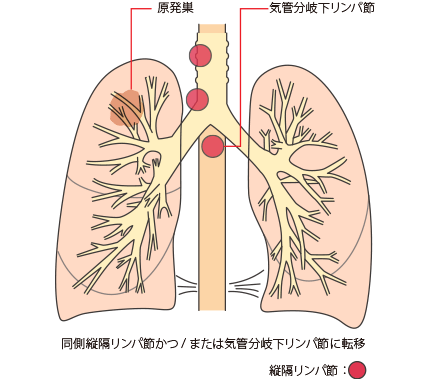

N2

同側縦隔かつ/または気管分岐下リンパ節への転移

N1は、最初にできたがん(原発巣)と同じ側の気管支周囲や肺門または肺内リンパ節に転移があることです。

N2は、原発巣と同じ側の縦隔リンパ節または気管支が分かれる部位のリンパ節に転移があることです。

図は、原発巣と同じ側の縦隔リンパ節に転移がある例です(N2)。

図は、原発巣と同じ側の縦隔リンパ節に転移がある例です(N2)。